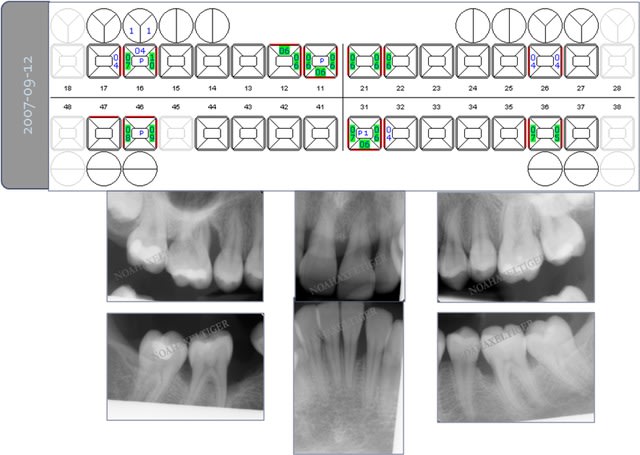

Paro ultra agressive chez une jeune femme de 30 ans.

Cas 2 (parodontite aggressive sur une jeune fille de 13 ans)

Photos initiales c6c2bg - Eugenol

Bilan initial nhvmno - Eugenol

Photos  1an drrxtl - Eugenol

Comparaison bilan rx bix6qa - Eugenol

Bilan de sondage  1 an muiwyr - Eugenol